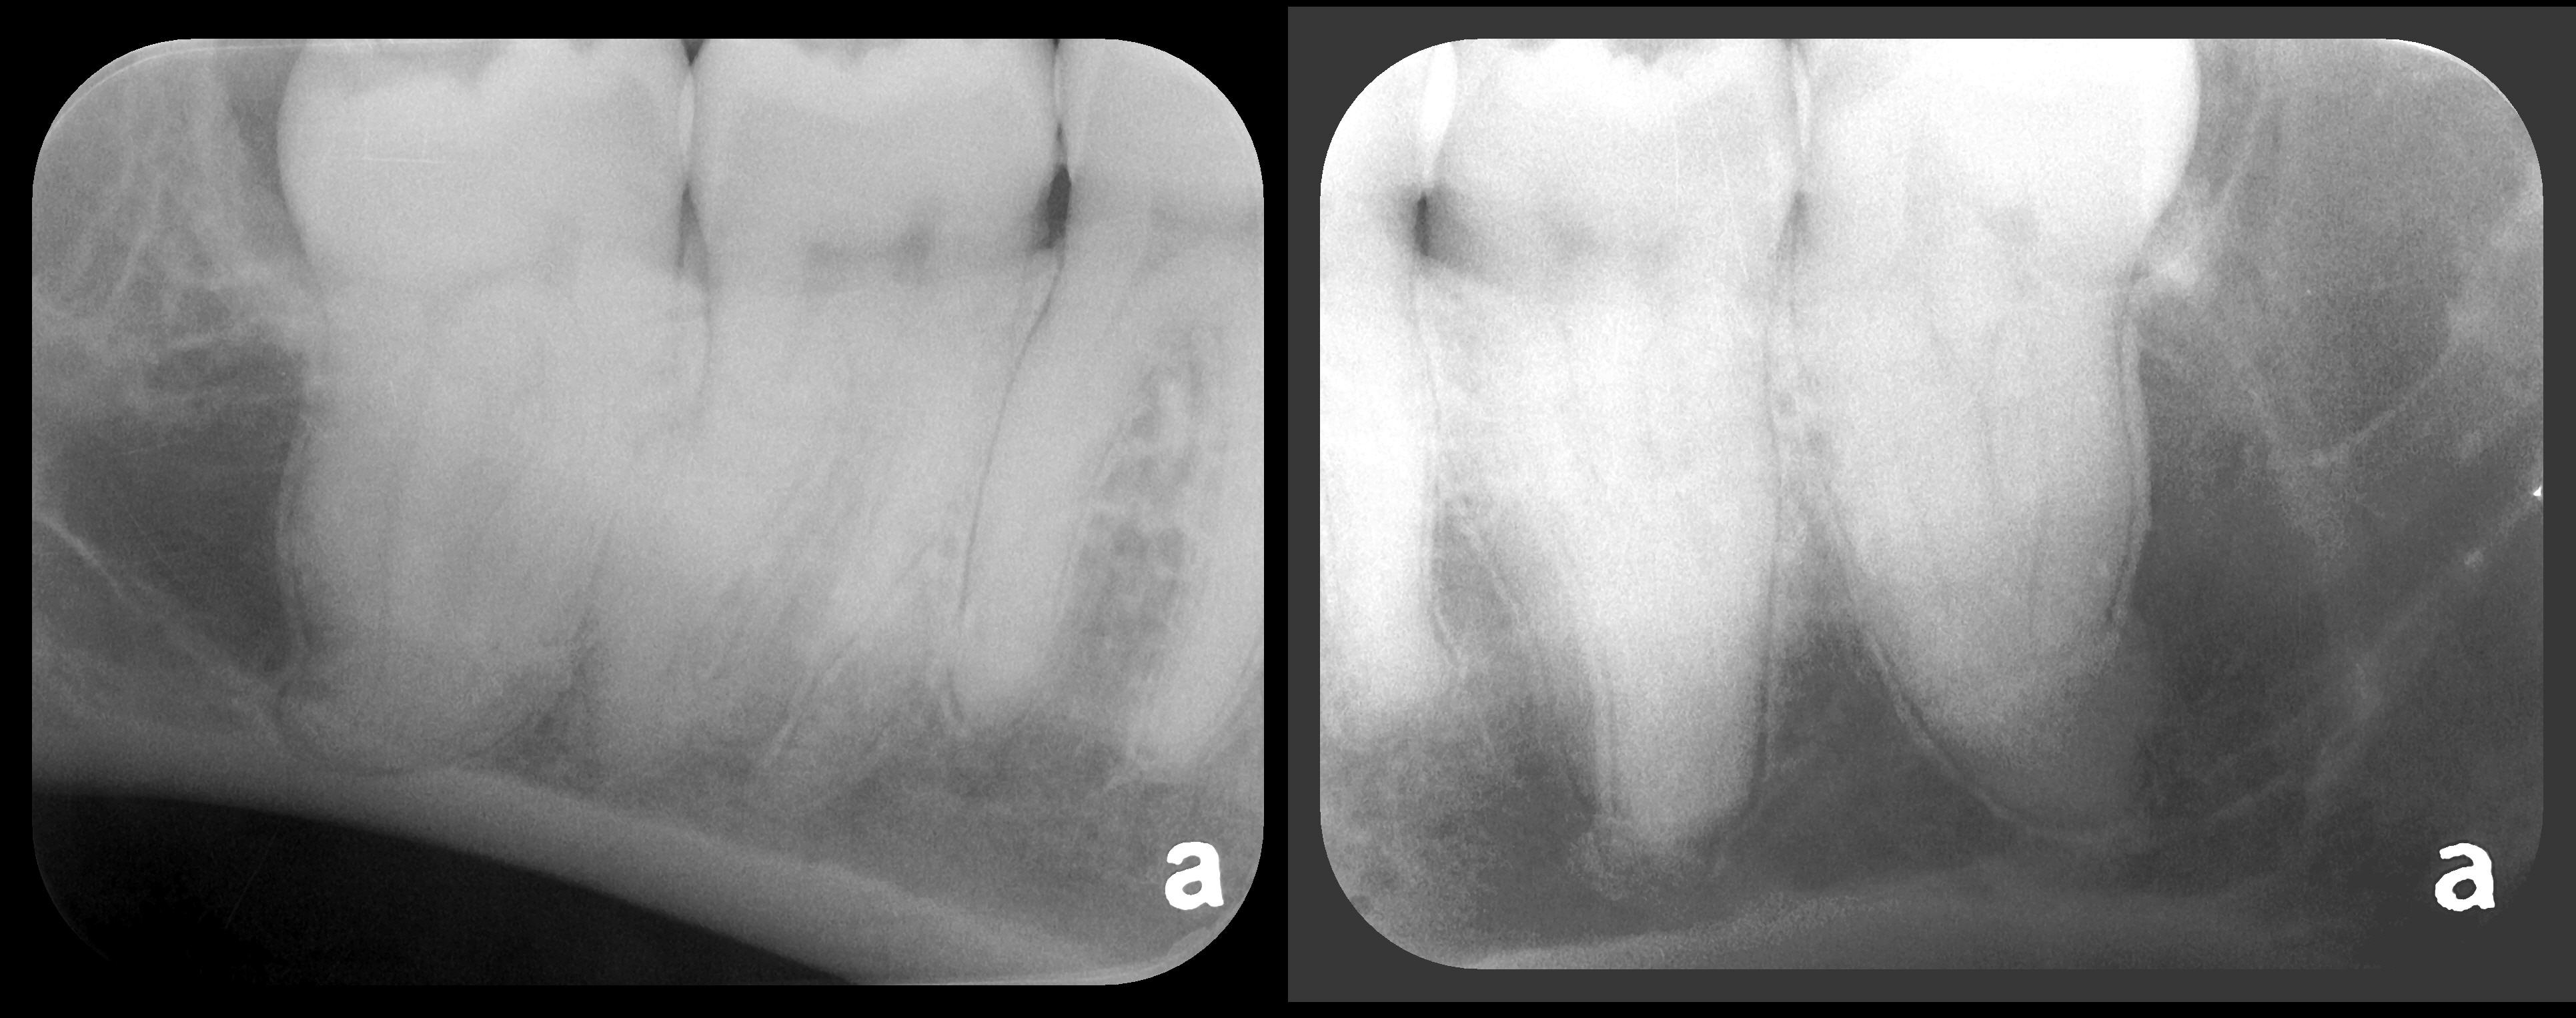

Fig 2. Left: PSP vertical PA radiograph of

maxillary bicuspid area demonstrating full root structure, several millimeters of bony anatomy beyond apices and maxillary sinus. Tooth No. 4 may be

traumatized as periodontal ligament is widened. Right: PSP horizontal PA radiograph of maxillary bicuspid area. Tooth No. 12 shows widened apical

periodontal ligament presumably caused by deep restorative filling. Some loss of supporting bone is evident interproximally, especially pronounced

between tooth Nos. 14 and 15.

Figure 2